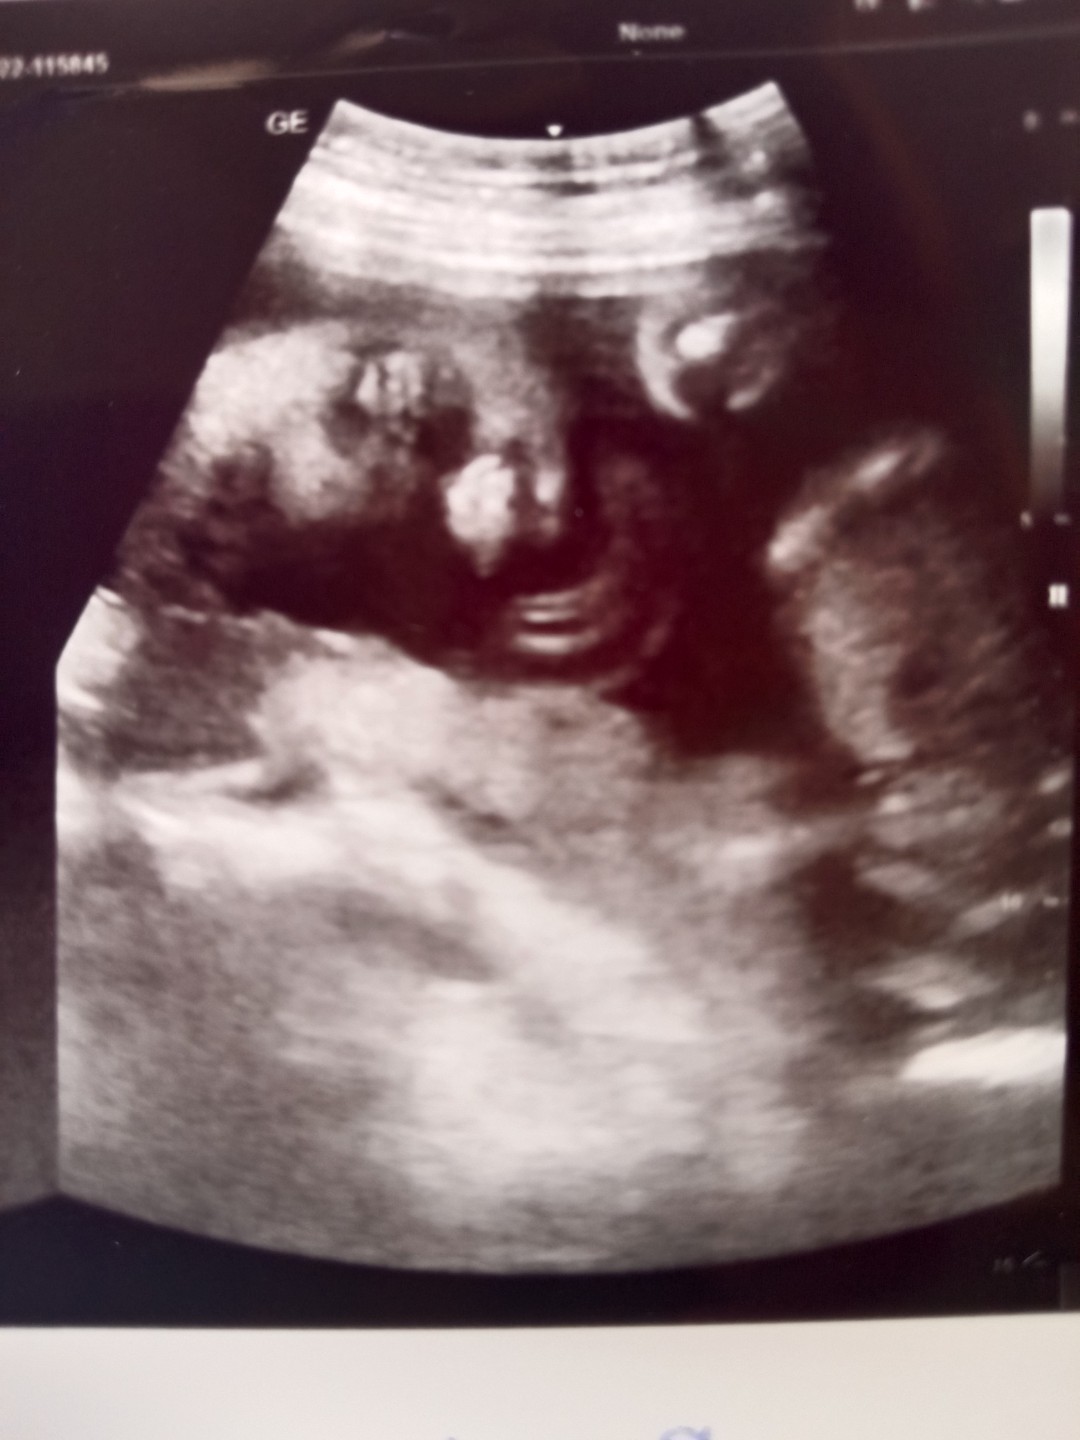

เอาภาพอัลตราซาวด์มาอวดจ้า บ้านนี้แลบลิ้นให้ป้าหมอไป1ที แถมเตะโชว์ไป1ที5555ป้าหมอบอกอาจจะดื้อนะ #ลูกสาว #ท้องแรก

ท้องแรกค่ะ 22 week ค่ะ ลูกชาย

ท้องแรกค่ะ ลูกสาว 22+5w.